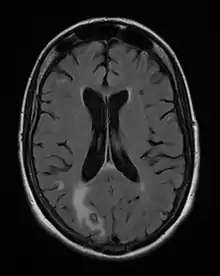

Acute toxoplasmosis is often asymptomatic in healthy adults.[13][14] However, symptoms may manifest and are often influenza-like: swollen lymph nodes, headaches, fever, and fatigue,[15] or muscle aches and pains that last for a month or more. It is rare for a human with a fully functioning immune system to develop severe symptoms following infection. People with weakened immune systems are likely to experience headache, confusion, poor coordination, seizures, lung problems that may resemble tuberculosis or Pneumocystis jiroveci pneumonia (a common opportunistic infection that occurs in people with AIDS), or chorioretinitis caused by severe inflammation of the retina (ocular toxoplasmosis).[15] Young children and immunocompromised people, such as those with HIV/AIDS, those taking certain types of chemotherapy, or those who have recently received an organ transplant, may develop severe toxoplasmosis. This can cause damage to the brain (encephalitis) or the eyes (necrotizing retinochoroiditis).[16] Infants infected via placental transmission may be born with either of these problems, or with nasal malformations, although these complications are rare in newborns. The toxoplasmic trophozoites causing acute toxoplasmosis are referred to as tachyzoites, and are typically found in various tissues and body fluids, but rarely in blood or cerebrospinal fluid.[17]

Due to the absence of obvious symptoms,[13][14] hosts easily become infected with T. gondii and develop toxoplasmosis without knowing it. Although mild, flu-like symptoms occasionally occur during the first few weeks following exposure, infection with T. gondii produces no readily observable symptoms in healthy human adults.[7][20] In most immunocompetent people, the infection enters a latent phase, during which only bradyzoites (in tissue cysts) are present;[21] these tissue cysts and even lesions can occur in the retinas, alveolar lining of the lungs (where an acute infection may mimic a Pneumocystis jirovecii infection), heart, skeletal muscle, and the central nervous system (CNS), including the brain.[22] Cysts form in the CNS (brain tissue) upon infection with T. gondii and persist for the lifetime of the host.[23] Most infants who are infected while in the womb have no symptoms at birth, but may develop symptoms later in life.[24]

- Nawaz Khan, A (2015). "Imaging in CNS Toxoplasmosis". Medscape Web Site.

The seroprevalence of T. gondii in humans varies between 10 and 70% worldwide, depending on the region and increases significantly with age. Upon infection, the parasites persist as intraneuronal cysts in the central nervous system (CNS) for the lifetime of the host (1, Figure 1). Until recently, parasite persistence in healthy individuals was regarded as clinically asymptomatic. However, in the last decade, several reports have indicated that chronic cerebral toxoplasmosis may impact on the behaviour of its host (2).